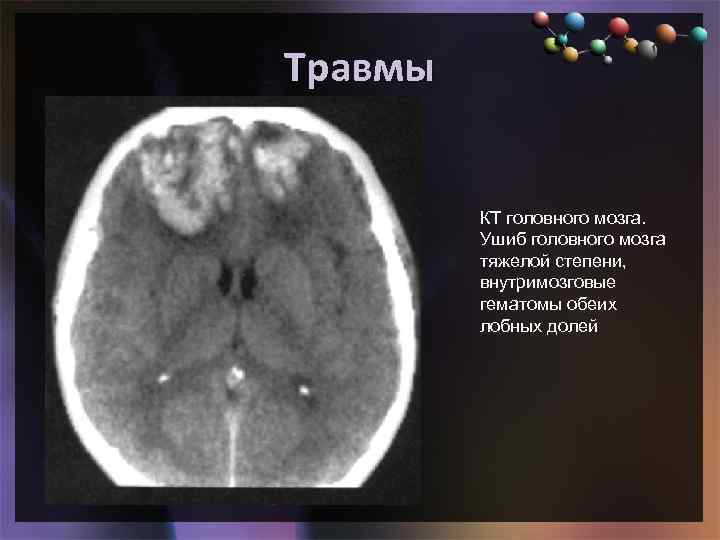

Травмы • Подзаголовок слайда КТ головного мозга. Ушиб головного мозга тяжелой степени, внутримозговые гематомы обеих лобных долей

Травмы • Подзаголовок слайда КТ головного мозга. Ушиб головного мозга тяжелой степени, внутримозговые гематомы обеих лобных долей